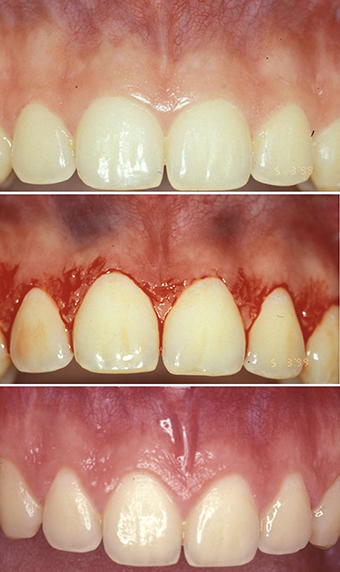

Gingivectomy (see Figure 1) is a surgical procedure that involves the excision of supracrestal gingival tissue while maintaining the integrity of the supracrestal tissue attachment. This technique is indicated when the distance between the planned gingival margin and the alveolar bone crest is at least 3mm, making flap elevation unnecessary. Gingivectomy is commonly performed using a scalpel, electrosurgery, or laser devices, each tool offering specific advantages in terms of precision, haemostasis, and postoperative comfort. However, gingivectomy is limited to cases in which osseous recontouring is not required and where sufficient keratinized tissue remains after surgery.